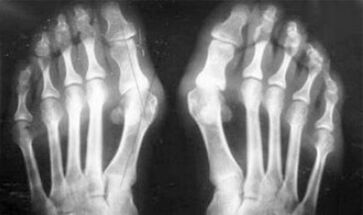

As you can see, differences in symptoms are insignificant: in both cases there is pain, stiffness and fatigue.Arthritis and arthrosis can affect different joints in the human body.With damage to the spine and intervertebral discs, osteochondrosis develops - is similar to arthrosis.Depending on the place of the disease, ankle arthrosis, shoulder, hip joints and so on is distinguished.